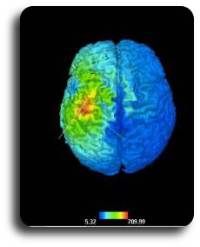

The Softaxic Optic system is a sophisticated system for stereotaxic neuronavigation.

It includes an integrated and intuitive setting for Transcranial Magnetic Stimulation (TMS), with particular attention for the TMS-EEG studies. The system is suited for the majority of magnetic stimulators on the market.